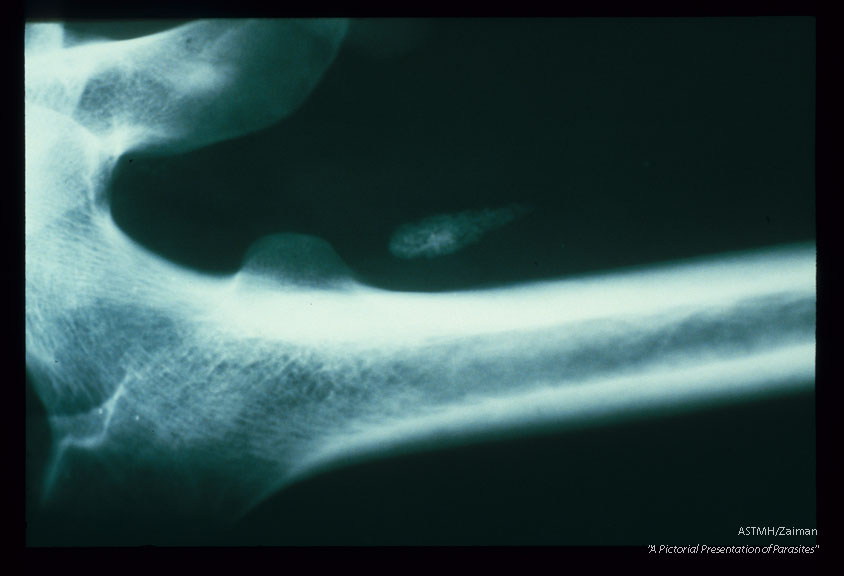

Frontal view of the thigh. An irregularly coiled white line medial to the femur represents a calcified adult in the lymphatics.

Wuchereria bancrofti

Description: Frontal view of the thigh. An irregularly coiled white line medial to the femur represents a calcified adult in the lymphatics.